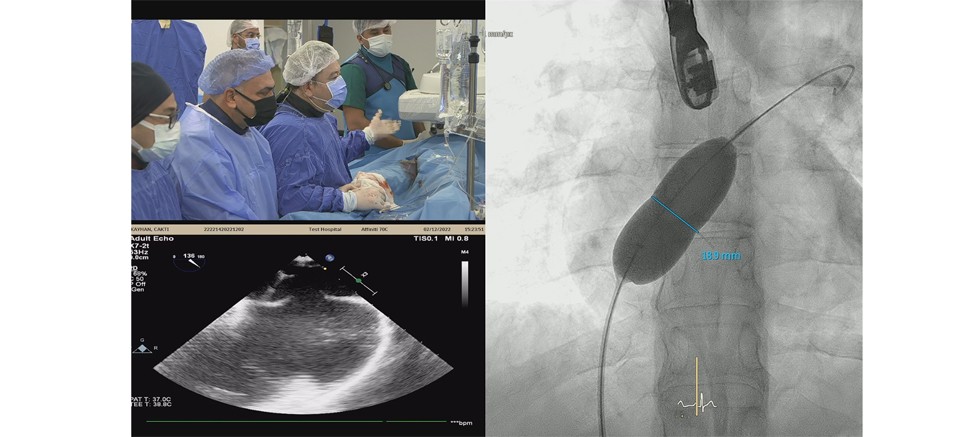

Prof. Dr. Öztekin Oto ve Prof. Dr. Ali Oto tarafından kurulan Türkiye Kalp ve Sağlık Vakfı tarafından 18.si düzenlenen “Kardiyoloji ve Kardiyovasküler Cerrahi’de Yenilikler Kongresi” 1-4 Aralık tarihlerinde Antalya Belek’te gerçekleştirildi. Kongre kapsamında Akdeniz Üniversitesi Hastanesi Tıp Fakültesi Kardiyoloji Bölümü Anjiyo Laboratuvarı’nda 10 adet kompleks girişimsel kardiyoloji işlemi yapıldı. Bu, 10 işlem canlı yayın aracılığıyla kongre katılımcıları tarafından izlendi.  Dört gün süren kongrenin ikinci günü 6, üçüncü günü 4 olmak üzere toplam 10 girişimsel kardiyoloji vakası başarıyla gerçekleşti.

Kongreye Patrick Peirer, Joe Coselli, Joe Bavaria gibi dünyaca ünlü kalp damar cerrahları da katıldı.  Kongre hakkında bilgi veren Tıp Fakültesi Öğr. Üyesi Prof. Dr. Umuttan Doğan, “Akdeniz Üniversitesi Tıp Fakültesi Kardiyoloji Bölümü olarak Türkiye Kalp ve Sağlık Vakfı tarafından 18.si düzenlenen ‘Kardiyoloji ve Kardiyovasküler Cerrahide Yenilikler Kongresi’nin ikinci ve üçüncü gününde kardiyoloji ile ilgili kompleks vakaların yapıldığı operasyonlara ev sahipliği yaptık. Anjiyo Laboratuvarımızda canlı yayında, kendi branşında hem dünyaca hem ulusal düzeyde tanınmış kardiyolog ve kardiyovasküler cerrah meslektaşlarımızla tartışarak yaptığımız vakaların tamamını başarıyla sonuçlandırmanın gururunu yaşıyoruz.” diye konuştu.

Akdeniz Üniversitesi’ndeki canlı yayınlarda Prof. Dr. Ömer Göktekin, Prof. Dr. Nihat Kalay, Prof. Dr. Ertuğrul Okuyan, Prof. Dr. Engin Bozkurt gibi dünyaca tanınan kardiyologlarımız girişimsel işlemleri başarıyla gerçekleştirdiler. Kongrede kalp ve damar cerrahisi hastalıkları ile ilgili kompleks vakaların konuşulup tartışıldığını belirten Prof. Dr. Umuttan Doğan, “2 gün boyunca günlük hayatta karşılaşılan ya da nadir görülen kompleks vakaları alanında tanınmış meslektaşlarımızla canlı yayında eş zamanlı olarak bilimsel veriler ışığında tartıştık. Hastalarımızı tamamen bilimsel kurallara uyarak tedavi ettik. Akdeniz Üniversitesi olarak tüm hastalarımızı sağlıklarına kavuşturmanın sevincini yaşıyoruz.” ifadelerini kullandı.